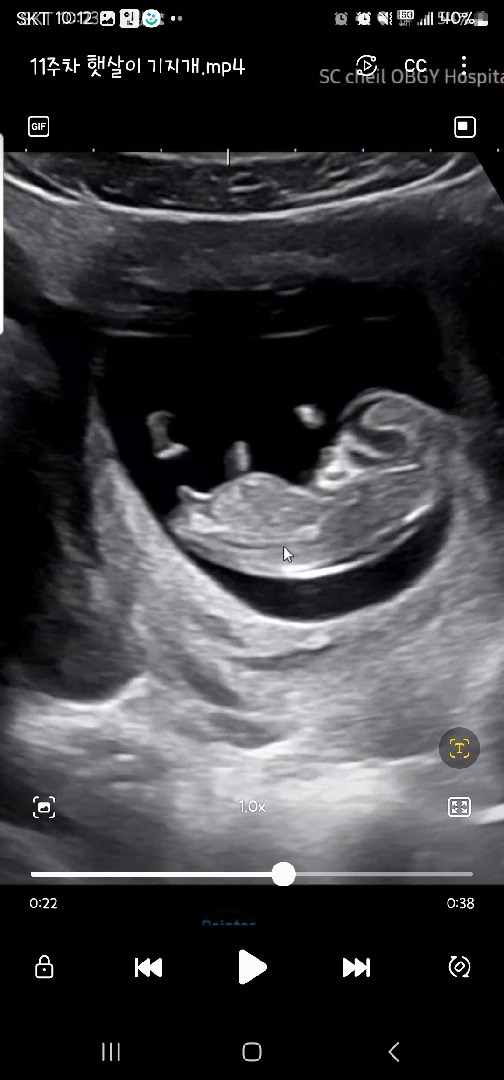

11주차 초음파!아들일까요 딸일까요

11주차인데 각도법으로 봤을때 뭘지! 딸같기도하고!